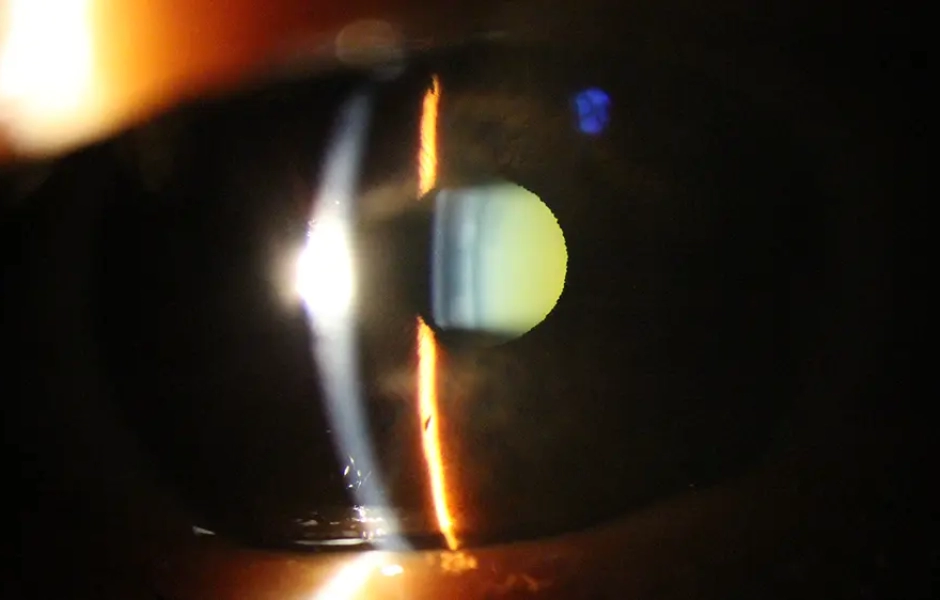

Nossos TratamentosTratamentos TodosCirurgiasOftalmologia ClínicaRecomendações Avaliação clínica dos olhos Oftalmologia Clínica Prescrição de óculos Oftalmologia Clínica Cirurgia Refrativa Cirurgias Catarata Cirurgias Ceratocone Cirurgias Cuidados anestésicos Recomendações Cuidados pós-operatórios Recomendações